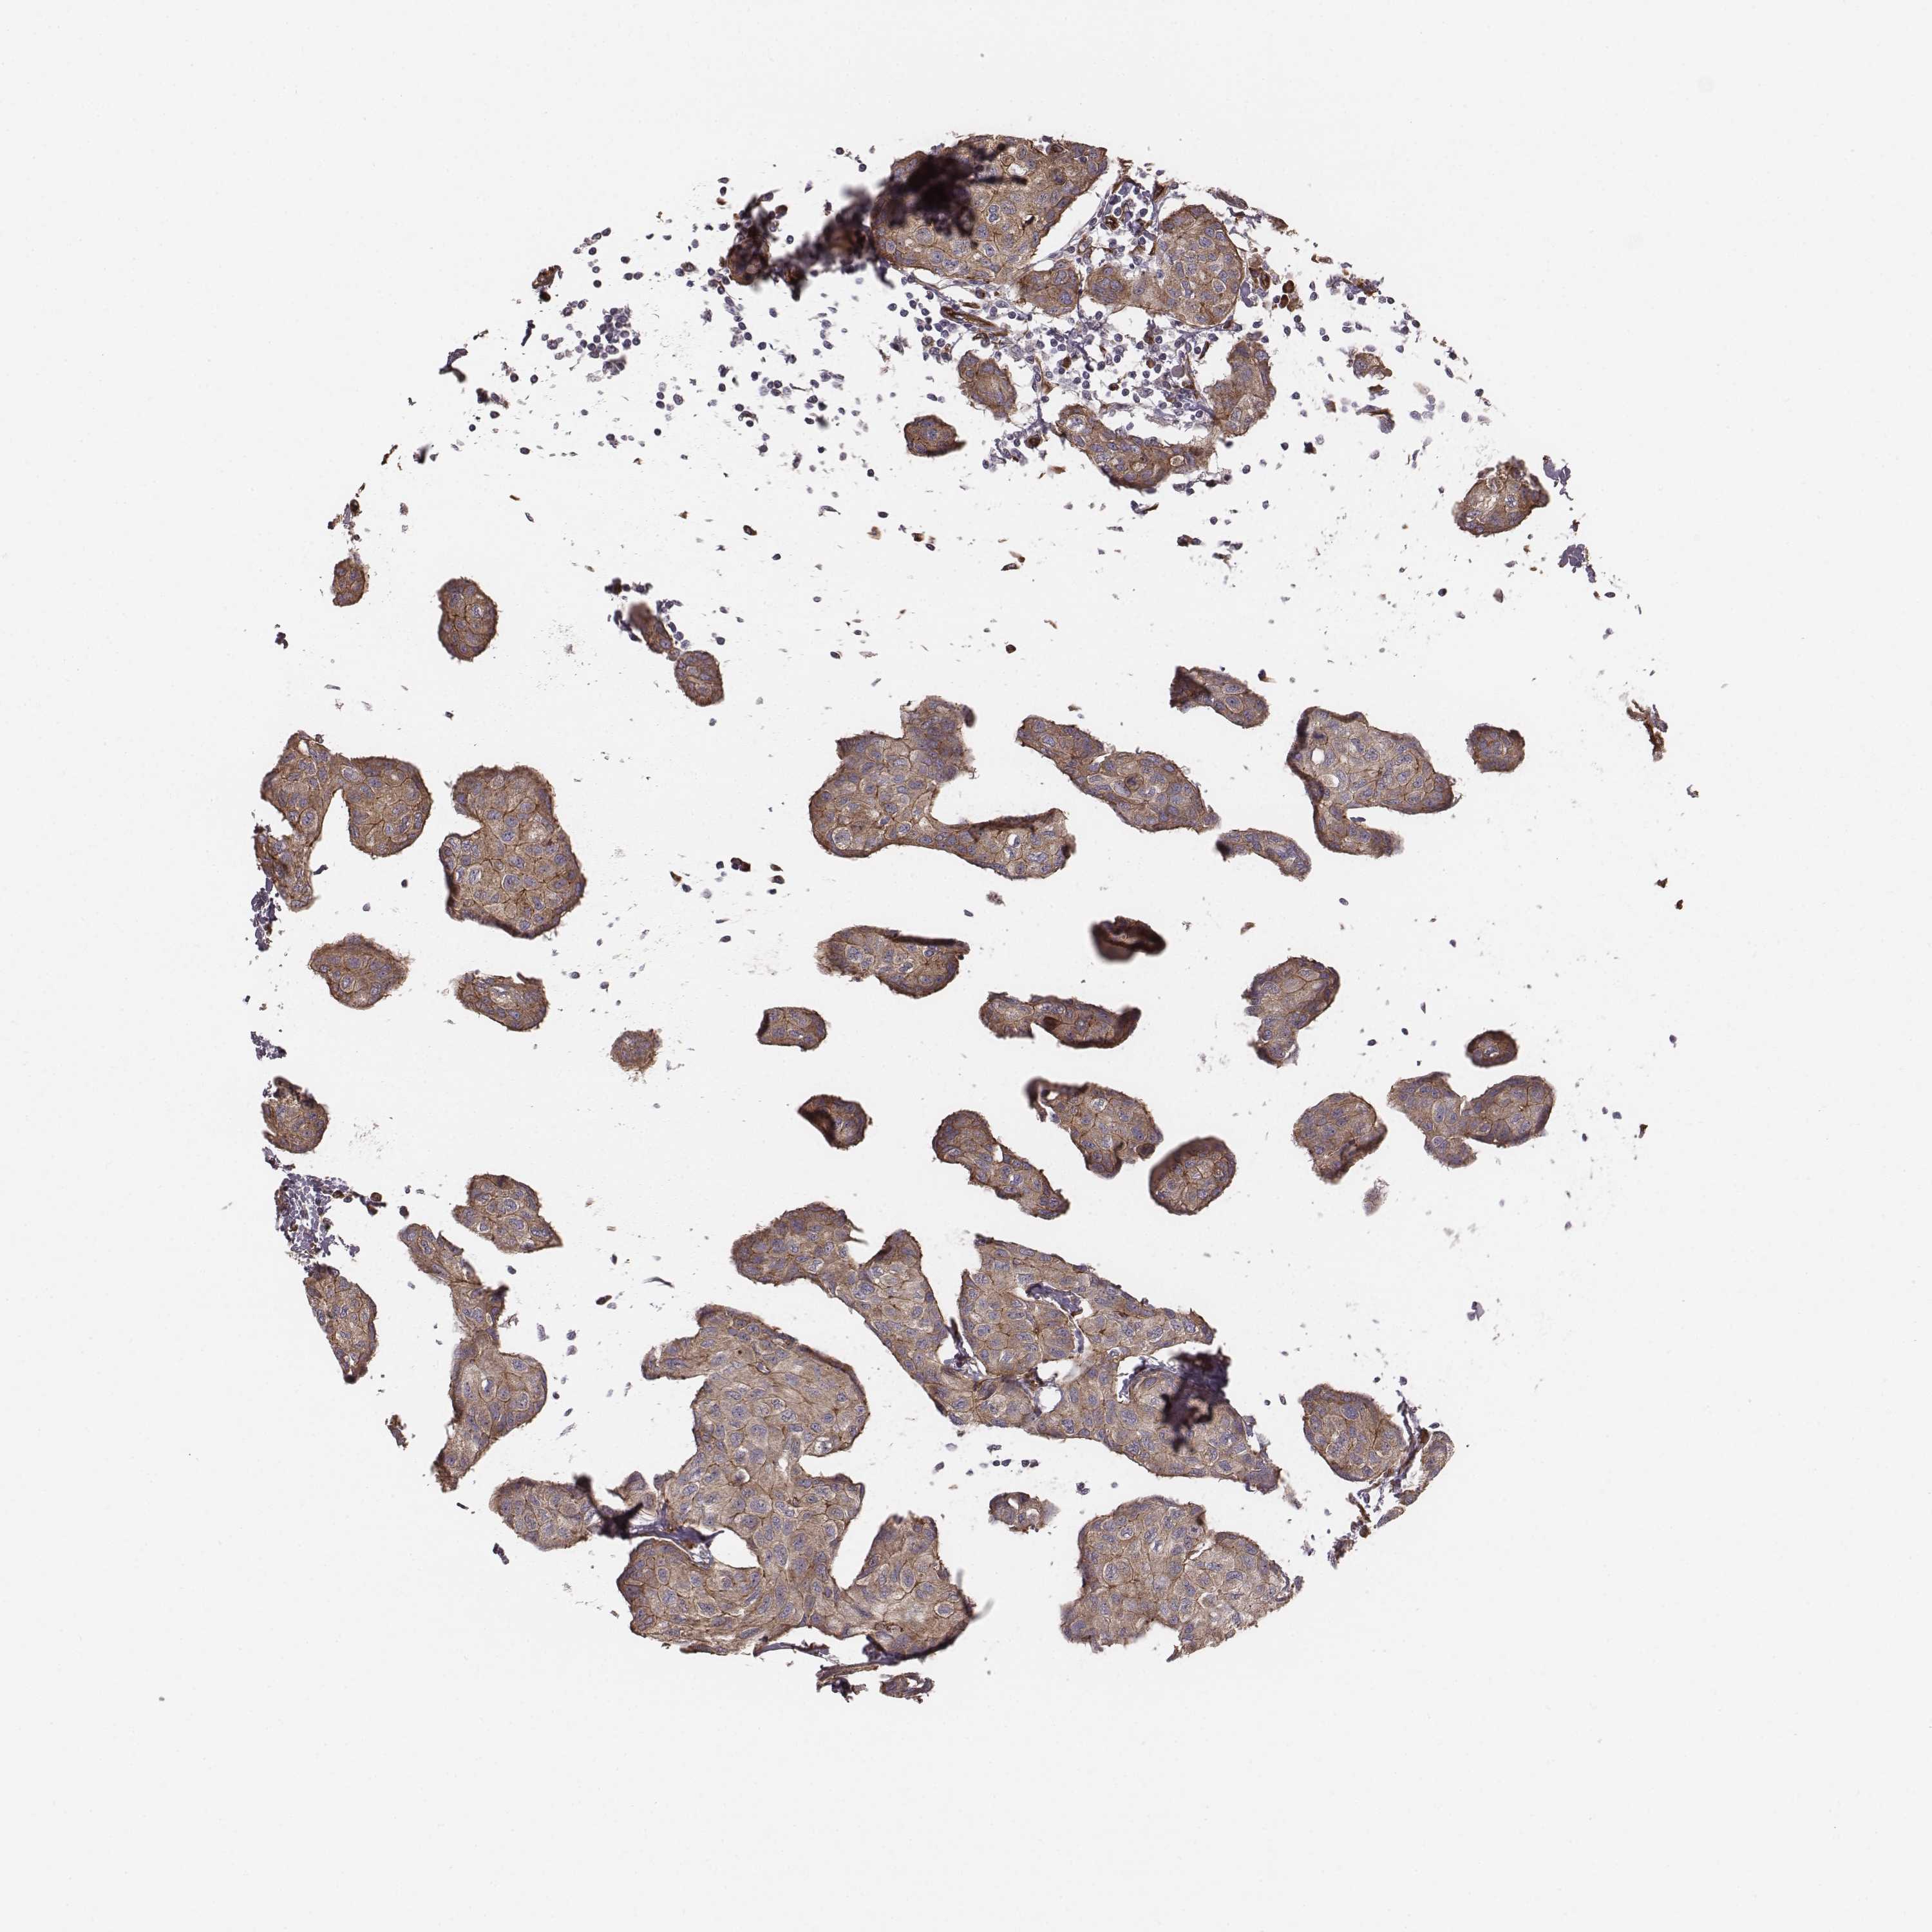

BRCA TCGA BRCA VALIDATION PROTEIN EXPRESSION